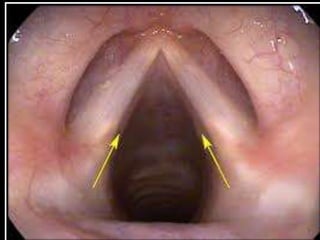

• Our throat has larynx. Larynx also called voice box. It is

• It is a box like structure with walls of tough tissue. Inside two

fold of tissue, there is a gap. They are called vocal chord.

• When we breathe, the vocal chords become loose and the gap

between them increases.

• When we talk, shout or sing, our chords become tight and

hence they vibrate and produce sound.

HUMAN BEING • Humanbeings produce sound when our vocal vibrates on blowing air through them by our lungs. • Our throat has larynx. Larynx also called voice box. It is designed to produce voice. • It is a box like structure with walls of tough tissue. Inside two fold of tissue, there is a gap. They are called vocal chord. • When we breathe, the vocal chords become loose and the gap between them increases. • When we talk, shout or sing, our chords become tight and hence they vibrate and produce sound.